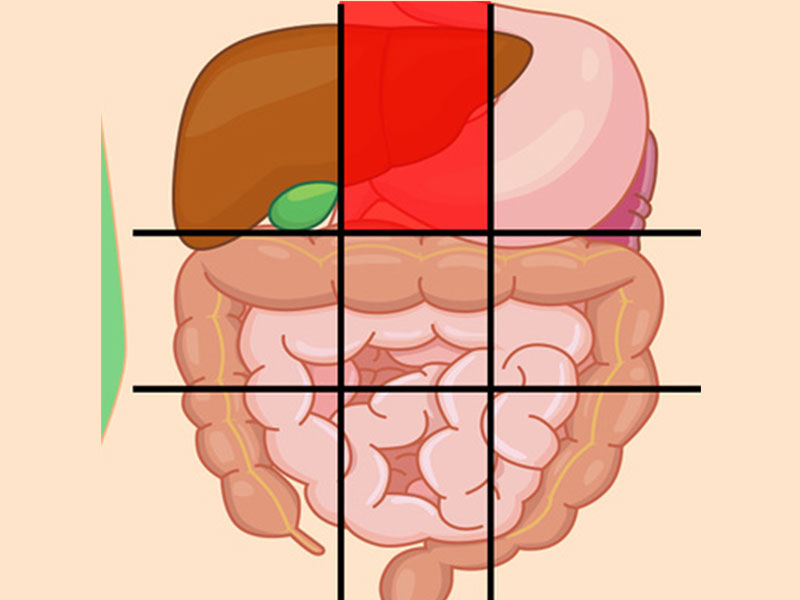

درد شکم در نواحی مختلف نشانه چیست؟

محل درد در شکم ممکن است سرنخی برای علت آن درد باشد که در زیر به بررسی آنها میپردازیم:

درد بالای شکم نشانه چیست؟

این ناحیه شامل لوزالمعده و بخشی از روده کوچک میباشد.

- پانکراتیک (التهاب لوزالمعده)

- فتق اپی گاستریک

- سنگهای صفراوی

- حمله قلبی

- هپاتیت (التهاب کبد)

- ذاتالریه

درد مرکز شکم نشانه چیست؟

احساس ناراحتی در این بخش از شکم معمولاً با مشکلات در رودهها همراه است.

دلایل ناراحتی در این ناحیه شامل موارد زیر میباشد:

- آپاندیس

- گاستروانتریت (بیماری التهاب معده)

- التهاب روده

- انسداد روده

- جراحت

- اوره (جمع شدن مواد زائد در خون شما)

درد شکم سمت چپ بالا نشانه چیست؟

بخش اصلی معده انسان در سمت چپ شکم او قرار دارد همچنین قسمت بالایی سمت چپ شکم نزدیک به قلب است، بنابراین معمولاً احساس غیرمعمولی در این بخش نشاندهنده مشکل در این اندامها است.

علل عمده درد این ناحیه شامل:

- طحال بزرگشده

- انقباض مدفوع (مدفوع سفت شده که قابل دفع نیست)

- جراحت

- عفونت کلیه

- حمله قلبی

- سرطان

- التهاب معده